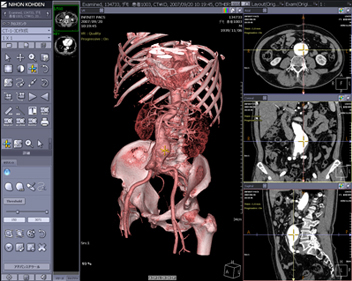

Dioramの最大の特徴は,PACS,3D作成機能(VR,MIP,MPR,仮想内視鏡),レポート機能,さらに心電図・動画ファイリングも含めて1つのシステムで構築可能な点にあります(図1)。1つのシステムで構築するメリットとしては,初期導入費用および保守費用などのコスト削減が挙げられます。また,2Dと3D表示が相互にリンクして表示される点もメリットの1つです(図2)。例えば,3Dで表示された病変部にポインタをマークすると,3D画像にリンクしてaxial断面像,coronal断面像,sagittal断面像それぞれにポインタが表示されるため,インフォームド・コンセントなどに利用可能です。さらに放射線科領域の検査データだけでなく,心電図波形,エコー動画,内視鏡画像やデジタルカメラで撮影した病理画像などの汎用画像ファイル(JPEG,BMP,TIFF)もファイリングすることで,部門システムにとどまらない院内のIT化を実現します。

![]() 図2 2Dと3Dのリンク表示 大きく表示されたVR画像と,画面右側に表示されたaxial, coronal, sagittalの各断面像はマウスクリックで相互にリンクしてカーソルが表示されます。 |